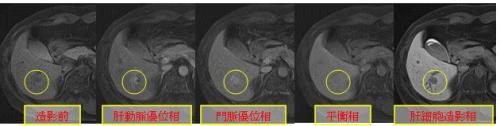

ダイナミックMRI

造影剤を早い速度で注入し、ある時間ごとに撮影していく方法です。時間ごとに同じところを撮影するので、時間ごとの造影剤到達具合により濃度差があらわれます。これにより、正常組織と病変部を造影剤の濃度差としてはっきり区別できる場合があります。

肝臓、すい臓、脾臓などの上腹部や頭部(下垂体)、前立腺や膀胱、腎臓など様々な部位をダイナミックMRIで撮影します。

(画像はGd-EOB-DTPA使用時の例)

○で囲まれた部分に腫瘍があります。造影剤が注入されると徐々に腫瘍が白くなっていきます。 しかし、平衡相になると肝臓の正常細胞との区別がつかなくなり肝細胞造影相では、腫瘍が黒く見えています。腫瘍の種類により時間ごとの造影剤の染まり具合が異なるのでこれらをみてどのようなものかを診断していきます。